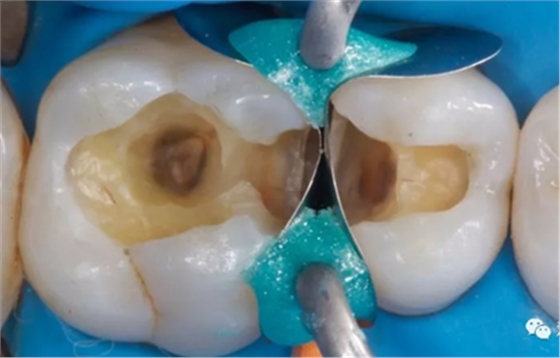

深齲應(yīng)拍攝 X 線片,以協(xié)助了解洞底與牙髓腔的關(guān)系,備洞時(shí)注意避讓。如 PPT2 圖示患者右下五的遠(yuǎn)中和右下六的近中 X 線片上可以看到低密度影像與牙髓組織接觸的很近,這是一個(gè)深齲。